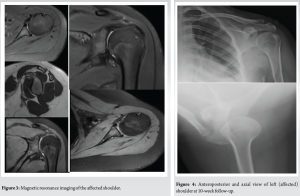

CT scan comparison with the opposite shoulder showed AP diameter of the left glenoid measured 19.7 mm. AP diameter of the right glenoid measured 21 mm. Comparative glenoid bone loss was pegged at 6%. There was mild flattening of the anterior margin of the glenoid. There was no scapular dyskinesia. The glenohumeral articulation was normal in the supine position on CT imaging. MRI revealed mild joint effusion with intact labrum, long head of the Biceps, and rotator cuff. The anterior and posterior bands of IGHL were intact.

Vertical humeral traction was reduced in an arm sling; there is no need for any reduction manoeuvers [9]. The Watson rehabilitation protocol was followed. It advises retraining specific scapular motor control before any rotator cuff/deltoid strengthening [10,11]. At the end of a 10-week period, follow-up radiographs revealed that the humeral head had been repositioned into the glenoid (Fig. 3 and 4), and the active range of motion had significantly improved to 90° abduction with possible overhead abduction. External rotation had also improved to 80°.